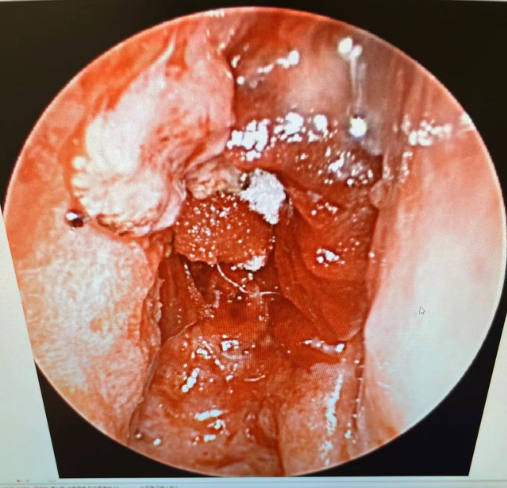

综合考虑后,蒋主任立即就给患者做了鼻内镜检查,并同时取了病理活检,内镜可见肿物已长满整个右侧鼻腔,伴少许黏稠鼻涕,已无通气空间,肿物表面呈白色荔枝肉样改变,乍一看确实很像“鼻息肉”。

▲鼻腔术后内镜

术中多点取材,避免漏诊可能性,最终病理提示:呼吸上皮乳头状瘤,部分呈内翻性生长,部分呈外生性生长,合并原位鳞状细胞癌,局灶见间质浸润。